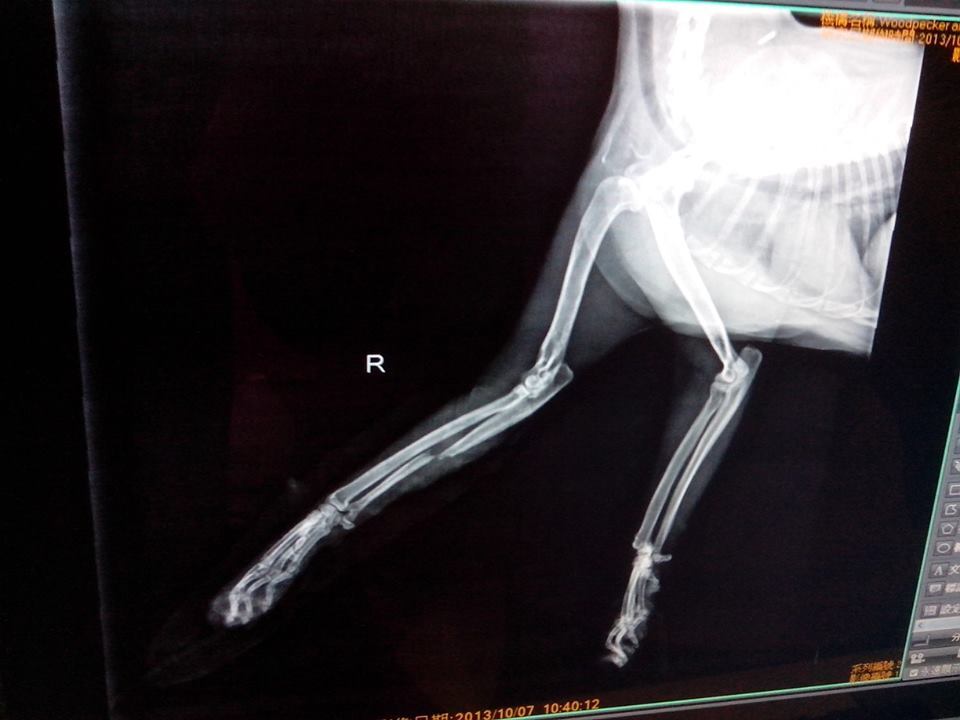

主題: 右前腳骨折的已結紮公貓-抓抓 申請者姓名: 程修芳 花色: 申請日期: 2013-11-02 08:36:06 申請者部落格: 申請者臉書網址: 所在縣市/合作醫院: 台南市/啄木鳥動物醫院 治療費用: 15970元 需求人數: 17人 已結案 (2014-01-10 18:02:14) 報名人員: ChiouYueh Shyu、Hui - Lan Zhuang(已付款)、ERic YU(已付款)、周小蕾(已付款)、WeiLin Chen(已付款)、WeiMin Lin(已付款)、Sky Lin(已付款)、謝小馬(已付款)、00(已付款)、Candace Shiue(已付款)、ginatw(已付款)、Helen Saroja Chen(已付款)、邱小祈(已付款)、nicole chen(已付款)、邱小祈、周星星(已付款)、周星星、Even Chen(已付款)、SASA(已付款)、小可(已付款)、 候補人員: 動物病情說明: 昨日發現自家附近已結紮公貓走路時右前腳一拐一拐的,因為抓抓很親人可以摸,所以大緻摸了一下發現有異樣, 經送啄木鳥醫院拍了X光, 發現右前腳有骨折現象, 需關籠休養,請問我可以申請醫助嗎? 動物近況說明: 經檢測2合一抓抓是愛滋猫, 所以即使固定了腳, 骨頭也沒有自動癒合, 所以必須要打鋼針固定, 目前已完成右前腳骨頭固定手術,已於 11/28日拆線, 在醫院休養.